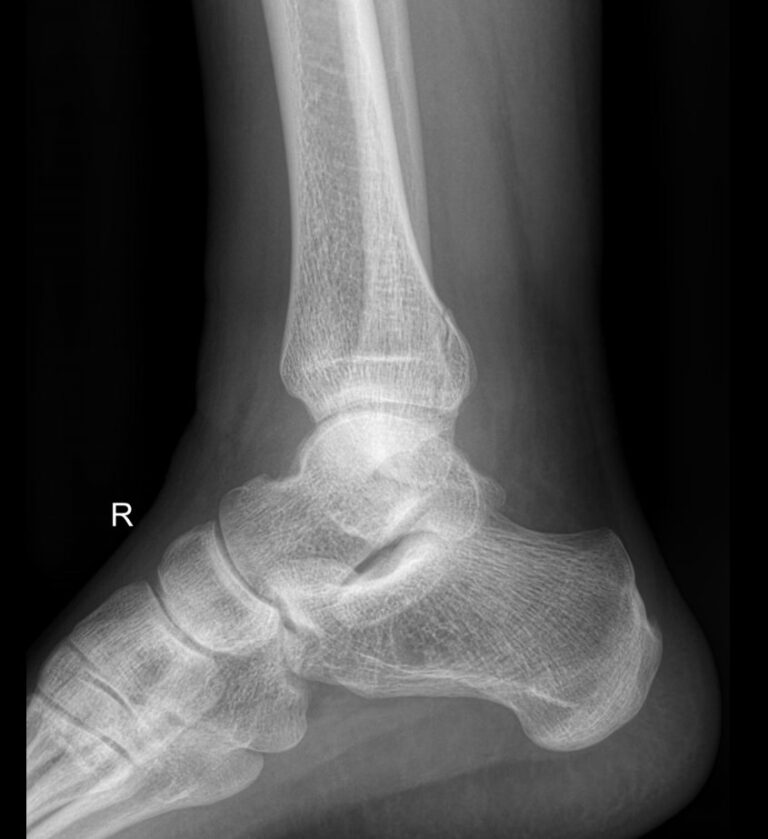

Голеностопные суставы отличаются сложным строением, в позволяющим стопе вращаться, сгибаться и разгибаться почти на 90о. Благодаря этому тело свободно перемещается в пространстве, меняет свое положение, поднимает собственный вес и дополнительный груз. Травмы голеностопных суставов встречаются также часто, как и хронические заболевания.

В качестве скринингового, а зачастую и единственного метода диагностики голеностопных суставов обычно используют рентген. Его вполне достаточно для визуализации внутреннего строения сустава и патологических изменений в нем. А цифровая нагрузка цифрового оборудования последнего поколения  несет минимум излучения и позволяет безопасно делать несколько снимков подряд.

Что покажет рентген голеностопных суставов

• Изменения, произошедшие в костной ткани элементов суставов ― разрежение, некроз, озлокачествление, склерозирование;

• Нарушение четкости контуров костных образований;

• Перелом, его местоположение, смещение отломков;

• Состояние суставных щелей ― сужение, расширение, скопление жидкости, обызвествление капсулы;

• Конгруэнтность суставных поверхностей или вывих;

• Состояние мягких тканей ― отеки, инородные тела.